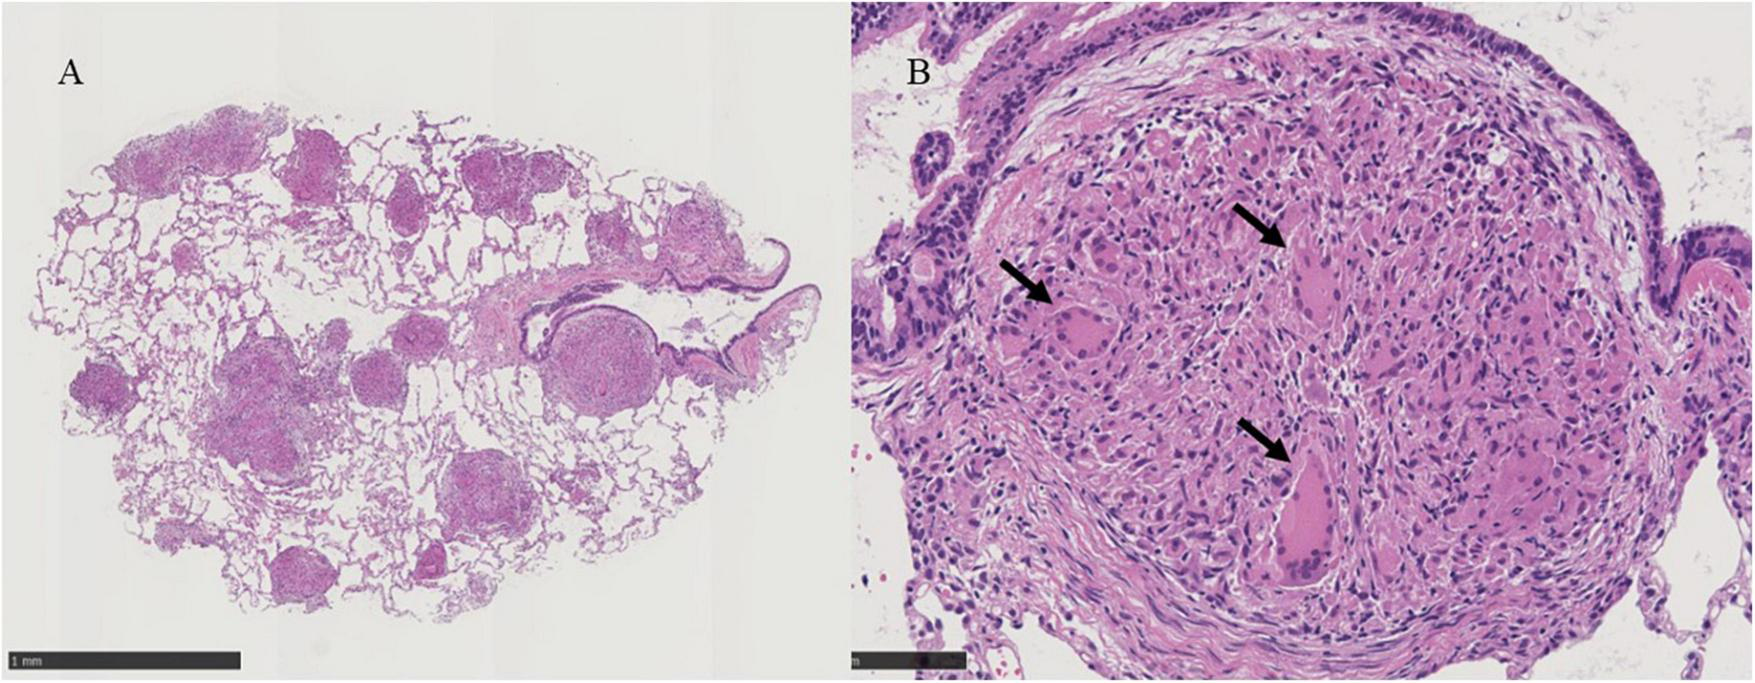

Bronchoscopy was performed on the lesions of the lung field and mediastinal lymph nodes on day X (Figure 1). The lumen of the main bronchus showed reticulated dilation of the capillaries, appearing like sarcoidosis. Bronchoalveolar lavage fluid (BALF) was collected from the left B5a, and 101/150 mL of lavage was recovered. The cell fraction of BALF was predominantly lymphocytes (87%), and the CD4/8 ratio was not elevated (0.97). Transbronchial needle biopsy (TBNA) was performed on longitudinal lymph nodes #7 and #2R, where access was feasible. TBLC was performed on right B8a, right B4a, and right B3a. In a previous report, granulomas from patients with BS displayed a distinct morphology characterized by large polycyclic granulomas with dense lymphocytic coronas, forming a large granulomatous complex without inter granulomatous sclerosis, indicating an exuberant chronic inflammatory response (4). In the present case, specimens obtained by TBLC were sufficiently large to observe complex of granulomas and inter granulomas, and those specimens showed non-caseating epithelioid granulomas scattered around the alveolar septum, bronchi, and vessels forming a large granulomatous complex without inter granulomatous sclerosis at low magnification (Figure 3A). At high magnification, prominent epithelioid cells and multinucleated giant cells around bronchioles were observed, similar to previous reports on polycyclic granuloma observed in lymph nodes or skin biopsy specimens from BS patients (4), but in the present case, they were not seen in granulomas with dense lymphocytic coronas (Figure 3B). TBNA specimens contained epithelioid cells. The cultures of cells obtained from saline for washing needle of TBNA and for probe of TBLC, BALF and an aspirated sputum sample through bronchoscopy did not reveal bacterial or fungus infections and mycobacterial infection by Ziehl-Neelsen stain and culture using mycobacterium growth indicator tube (MGIT) system. Based on clinical, hematological, and pathological findings, the lung lesions were diagnosed as pulmonary granulomas caused by BS. While an additional dose of prednisolone was considered for the therapy of cough and lung lesions, taking into account the lack of SpO2 decrease, the patient’s young age, the increased risk of adverse effects from additional prednisolone, the absence of infection and also the possibility of spontaneous resolution of granulomatous lesions, the patient was followed up for 2 months without escalating dose of prednisolone or additional immunosuppressant. Celecoxib, a cox-2 inhibitor, was additionally administered for arthralgia of the knees and wrists, and arthralgia was alleviated. Cough gradually decreased spontaneously subsequent two months (X+2M), and chest X-ray also showed a slight improving. However, after four months form bronchoscopic examination (X+4M), right knee and right wrist, proximal interphalangeal (PIP) joint pain and metacarpophalangeal (MP) joint pain were aggravated again. Since chief complaint of the patient was joint pain and prednisolone and methotrexate (MTX) and/or azathioprine were recommended for pulmonary sarcoidosis (5), MTX 4mg/2weeks was started for the arthralgia. The dose was subsequently increased, and pain was under control. No adverse effects due to MTX have appeared. Despite worsening arthralgia on the day X+4, cough and the lung lesions have remained without recurrence, and those were no subsequent deterioration. Changes in serum angiotensin converting enzyme (ACE) and soluble interleukin-2 receptor (sIL-2R) levels appeared to reflect well the manifestation of cough and lung lesions and their subsequent resolution (Figure 1).

FIGURE 3

(A) Histological examinations of the lung tissue obtained by transbronchial lung cryobiopsy show non-caseating epithelioid granulomas scattered around the alveolar septum, bronchi, vessels and large complex of granulomas without inter granulomatous sclerosis at X30 magnification, black scale bar = 1mm. (B) Prominent epithelioid cells and multinucleated giant cells around bronchioles are indicated by black arrows in the panel at X200 magnification, black scale bar = 100 μm.